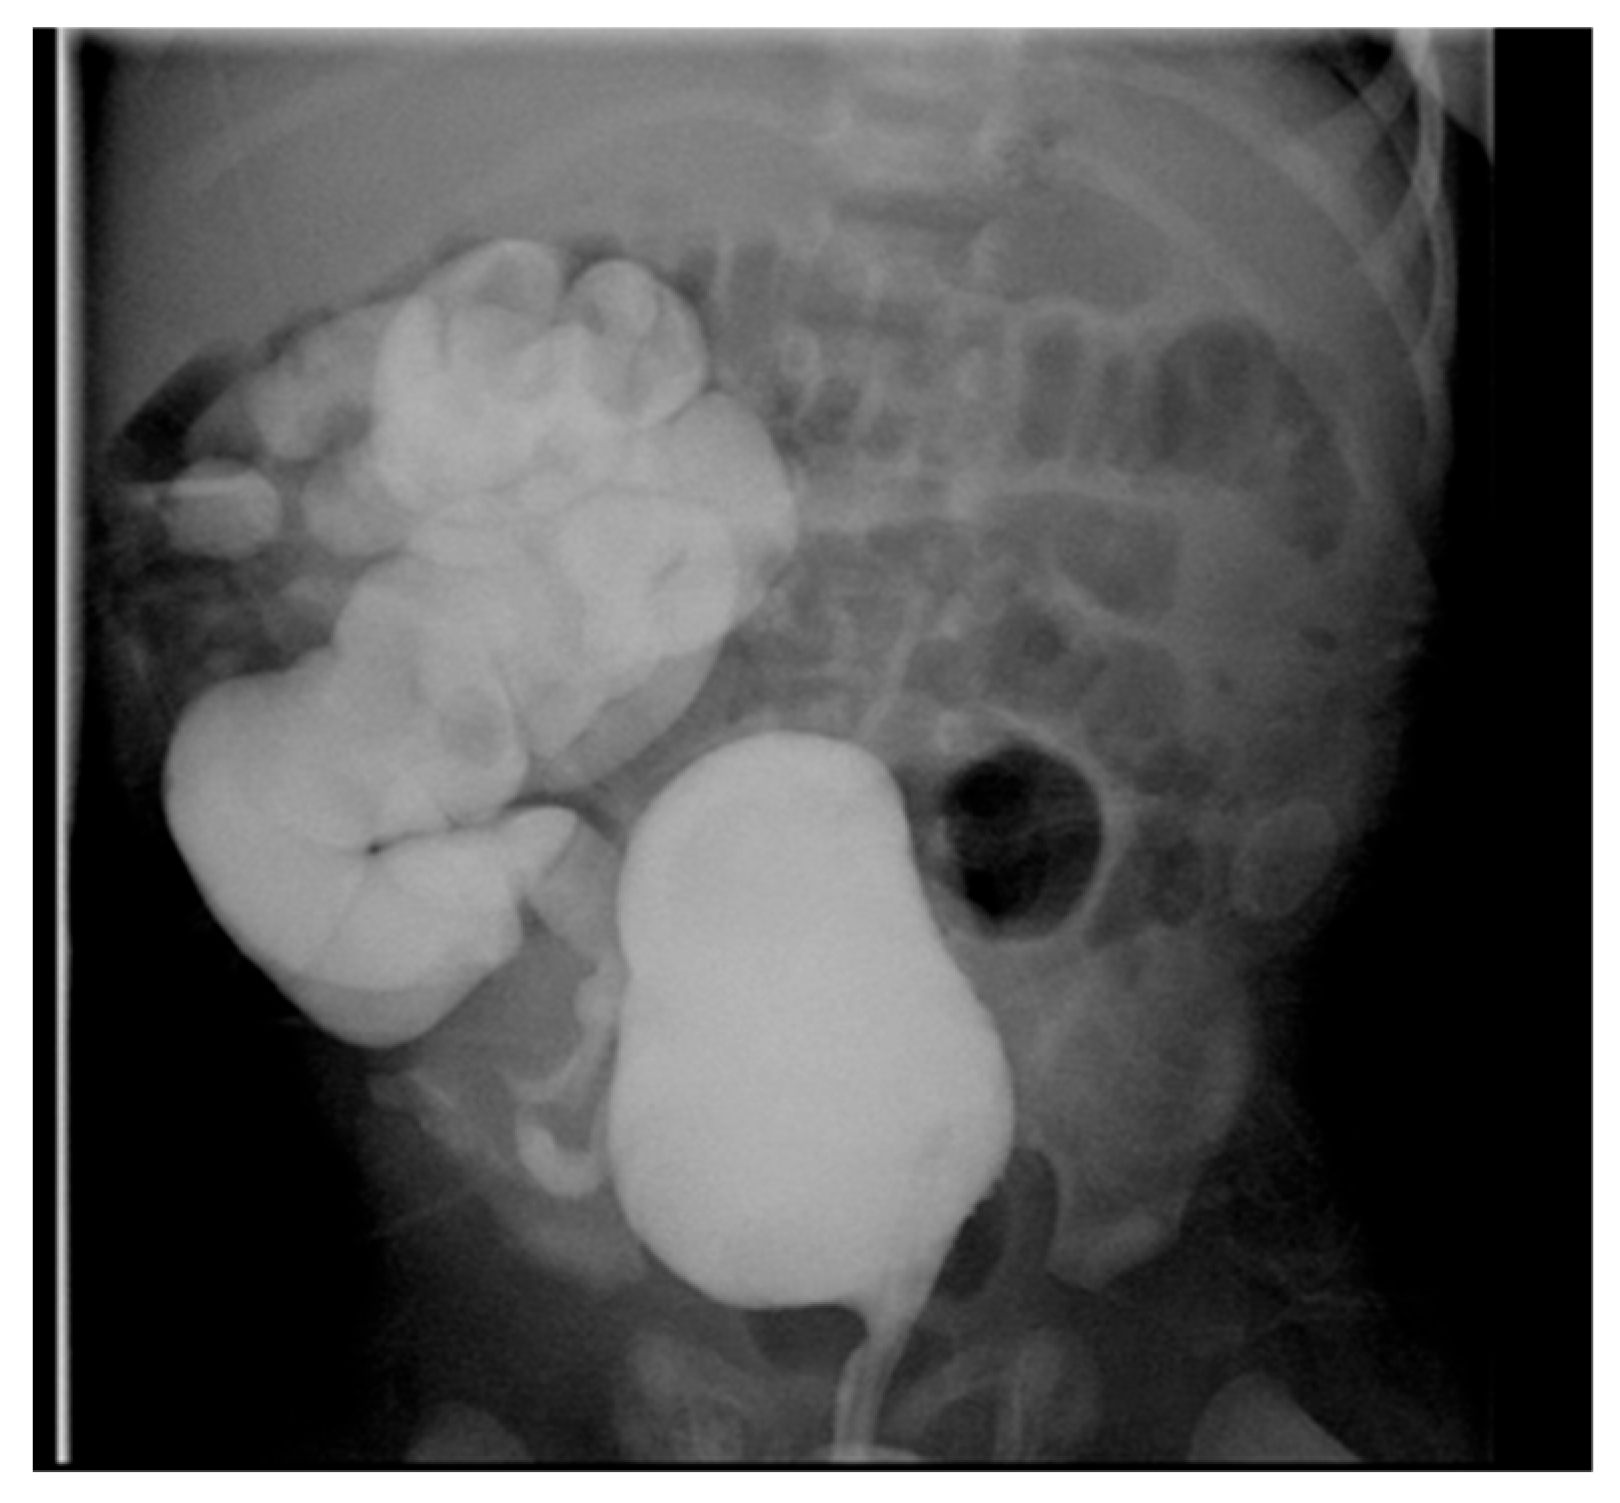

Figure 5. IVP shows right crossed renal ectopia (indicated by arrows).

IVP is useful for evaluating ureteroceles, renal scarring, ectopic ureters, and obstructive disease (Figure 5), but has been largely replaced by US, CT, MRI, and renal scanning.

US is typically diagnostic for these conditions, as it can identify the location and structure of the kidneys. However, additional imaging, such as intravenous pyelography (IVP), CT, MRI, or renal scintigraphy, may be needed for further confirmation and to assess any associated abnormalities or complications (Figure 5).